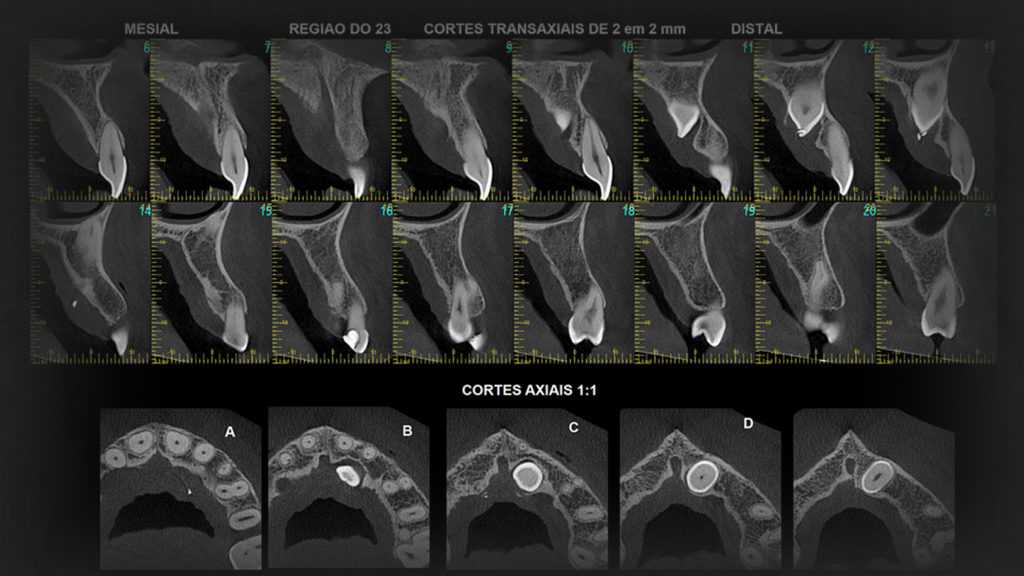

A Tomografia Computadorizada de Feixe Cônico (CBCT, do inglês Cone Beam Computed Tomography) foi desenvolvida especificamente para a área odontológica e maxilofacial.

Diferente da TC convencional, o Cone Beam utiliza um feixe de raios X em formato cônico, que gira 360 graus ao redor do paciente, capturando centenas de imagens em poucos segundos.

Contudo, essas imagens são processadas por softwares específicos, resultando em uma reconstrução tridimensional da região de interesse.

Por isso, essa tecnologia se tornou um marco na odontologia moderna, pois oferece alta qualidade de imagem com uma dose significativamente menor de radiação em comparação à tomografia convencional.